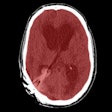

Head CT algorithm a step toward faster stroke care

October 6, 2016